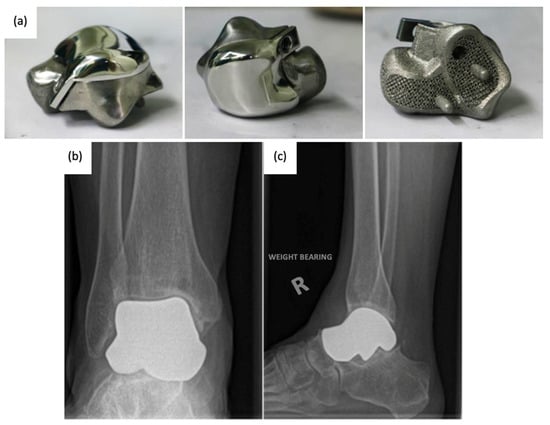

Since the talus is not stabilized by any muscular attachments, its positioning primarily depends upon the support of the surrounding bones and ligaments, and thus, the most important factor for prosthesis survival is implant congruence with articular surfaces []. Recently introduced third-generation TTA implants (Figure 9) are described as custom total talar prostheses, which circumvents the earlier concerns of loosening and sinking between the talar neck and prosthesis. Many groups have designed TTA implants using the patient’s healthy contralateral talus as a model for AM, which can be made into forms that may not have been possible to achieve using the current production method []. Custom third-generation TTA implants have been manufactured primarily by SLS, using materials including cobalt–chrome, nickel-plated cobalt, titanium alloy, and alumina ceramics. These implants have demonstrated retention of mobility, rapid pain relief, and preserved joint height, as well as a shorter duration of restricted weight bearing [,,,,]. A case series evaluating the outcomes of patients who underwent TTA with AM titanium or cobalt–chromium talus implant reported no complications at a mean follow-up of 36 months with preserved range of motion in the ankle and improved pain scores []. To date, there have been no issues of prosthesis size incongruence, but long-term follow-up is needed to evaluate the longitudinal durability of custom-made TTA implants and their effects on ankle and foot function. Potential complications of concern with third-generation TTA may involve displacement of the implant.

Figure 9. (a) 3D-printed third-generation total talus prosthesis and post-operative X-rays of implanted 3D-printed third-generation TTA prosthesis, (b) anterior–posterior, and (c) lateral views [,].